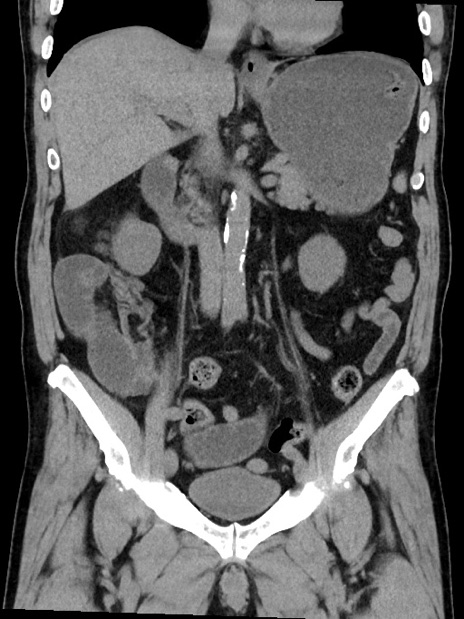

症例35(冠状断像)

【症例】70歳代 男性

【主訴】腹部膨満、嘔吐

【現病歴】昨日より腹部膨満感出現。本日増悪し、仙痛出現。嘔吐あり、受診。

【既往歴】糖尿病、胆摘後

【身体所見】BP 149/80mmHg、HR 74/min、BT 35.9℃、腹部:膨満、軟、圧痛なし。腸雑音減弱あり。上腹部正中切開瘢痕あり。

【データ】WBC 13500、CRP 1.72